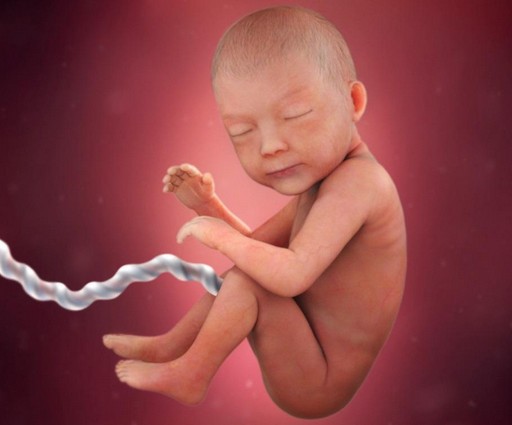

مراحل نمو الجنين بالصور

مراحل نمو الجنين بالصور ، بالطبع لا يمكن أن ننكر مدى الفرحة والسعادة التي يشعر بها الوالدان عند سماع خبر الحمل فتبدأ المرأة بتصور هذه القطعة التي تنمو في احشائها وتكبر يوماً بعد الآخر، ويبدأ الجنين بالنمو على مجموعة من المراحل في مجموعة من الشهور والأسابيع فإذا كانت لديك الرغبة في التعرف على هذه المراحل سيكون هذا المقال مرجع رائع لديك من دار الطب يعرفك بالتفصيل على مراحل نمو الجنين بالصور .

الأسبوع السابع والعشرون

خلال هذا الأسبوع يبدأ شكل الجنين بالوضوح ويصبح قريباً للشكل الذي يظهر به الجنين عند الولادة، ولكن مع اختلاف أنه صغير الحجم كما أ هناك بعض الأعضاء لم يكتمل نموها بعد مثل الرئتين والكبد، جدير بالذكر أن هناك حالات معينة يولد فيها الطفل خلال هذا الأسبوع ويعيش بشكل طبيعي جداً إذا تم الاهتمام والعناية به من قبل الأطباء بعد ولادته.

الأسبوع الثامن والعشرون

تبدأ جفون الطفل بالتفتح وتتشكل رموشه خلال هذا الأسبوع كما يبلغ وزنه 1 كيلو وكذلك يمكن ولادته بهذا الأسبوع وتصبح فرص حياته كبيرة بنسبة تتعدى ال90%.

هذا الأسبوع هو الأسبوع الذي يفترض أن تتم فيه الولادة ويكون حجم الجنين خلاله 50 سم ووزنه حوالي 2900 جم ويختلف الأحجام بفروقات بسيطة من جنين لآخر ولكن المشترك في الموضوع أن أجهزة الجسم اكتملت وأصبحت تعمل بصورة سليمة لا تؤثر على حياة الطفل بعد ولادته.